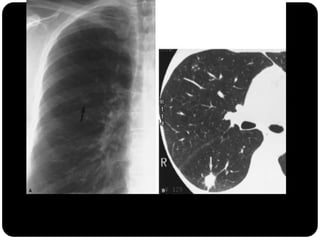

Sinal de árvore em brotamento

Perfusão em mosaico ( X vidro fosco)